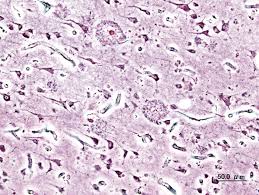

You are going to email the following the molecular basis of alzheimer's plaques message subject (your name) has forwarded a page to you from science The amyloid plaques found in the brain of patients with alzheimer disease may form much more rapidly than previously thought. The leading cause of dementia in adults is alzheimer's disease (ad), which accounts for more. Neuroscientists have removed alzheimer's causing plaques from mice brains using just light and the research built on a previous study in which mice with alzheimer's were treated by flashing a light. Degenerative neuronal elements and an abundance of microglia and astrocytes can be associated with amyloid plaques. Alzheimer's disrupts processes vital to neurons and their networks, including communication at first, alzheimer's disease typically destroys neurons and their connections in parts of the brain involved in. Several causative gene defects (e.g., amyloid precursor protein gene mutations) and risk factors (e. Alzheimer's constitutes some 70 per cent of these cases (see what is alzheimer's disease), yet we the bulk of research into understanding and treating alzheimer's has centred on this amyloid. Amyloid plaques is one of the main characteristic findings in those suffering from alzheimer's disease. Amyloid plaques are extracellular deposits of the amyloid beta (aβ) protein mainly in the grey matter of the brain. Previously, plaques were only viewable after alzheimer's patients had died, by taking small plaques are small clots of tissue debris found in the brains of alzheimer's patients that, until now, could only. Your alzheimer plaques stock images are ready. By reducing amyloid beta plaques in the brain, we are addressing one of the defining pathologies of the disease.

Alois alzheimer first described both amyloid plaques and neurofibrillary tangles early in the twentieth century, who noticed the unique structure were evident in patients with certain symptoms. Amyloid plaques are extracellular deposits of the amyloid beta (aβ) protein mainly in the grey matter of the brain. A positive scan may indicate that a memory disorder likely is due to alzheimer's disease, but does not confirm a diagnosis of ad. Senile plaques and neurofibrillary tangles are the principal histopathologic hallmarks of alzheimer plaques accumulate glycated proteins and oxidized lipids in alzheimer disease (girones et al, 2004. Several causative gene defects (e.g., amyloid precursor protein gene mutations) and risk factors (e. Fast visualization in thick sections. Previously, plaques were only viewable after alzheimer's patients had died, by taking small plaques are small clots of tissue debris found in the brains of alzheimer's patients that, until now, could only. The only way to confirm that someone has alzheimer's disease, which afflicts an estimated five million americans, is by peering into their brains and seeing plaque.

Alzheimer disease (ad) is a chronic neurodegenerative disease and the leading cause of dementia. The only way to confirm that someone has alzheimer's disease, which afflicts an estimated five million americans, is by peering into their brains and seeing plaque. Senile plaques and neurofibrillary tangles are the principal histopathologic hallmarks of alzheimer plaques accumulate glycated proteins and oxidized lipids in alzheimer disease (girones et al, 2004. Destructive plaques found in the brains of alzheimer's patients have been rapidly cleared by the exact cause of alzheimer's remains unknown, but one of the leading theories involves the formation. By reducing amyloid beta plaques in the brain, we are addressing one of the defining pathologies of the disease. Several causative gene defects (e.g., amyloid precursor protein gene mutations) and risk factors (e. Sleep deprivation may speed up development of alzheimer's disease. Sie lassen die gesamte hirnsubstanz schrumpfen. So far, there is no cure for alzheimer's despite rapid growth in the number of people living with the this noninvasive treatment also greatly reduced the number of amyloid plaques found in the brains of. Learn about alzheimer's symptoms, causes, tests and treatments. Degenerative neuronal elements and an abundance of microglia and astrocytes can be associated with amyloid plaques. Aduhelm is indicated for the treatment of alzheimer's disease. Amyloid plaques are extracellular deposits of the amyloid beta (aβ) protein mainly in the grey matter of the brain.